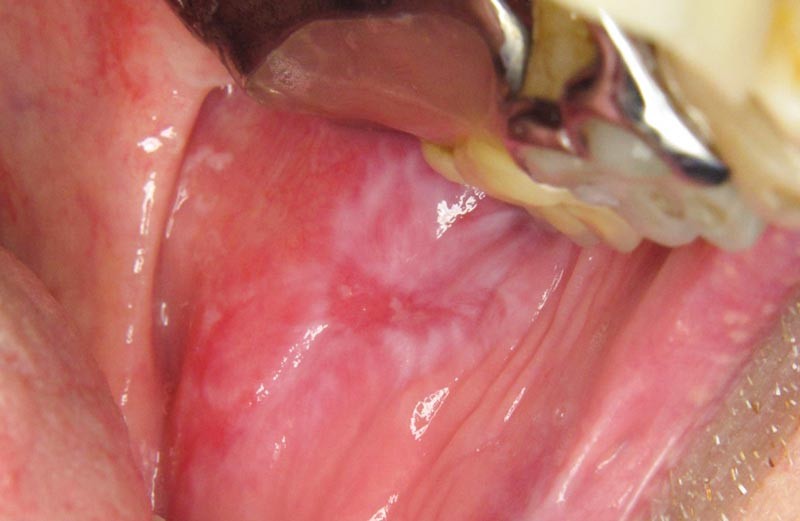

On observait une large plage érythémateuse et kératosique sur la joue gauche. En périphérie, la kératose avait un aspect dendritique. Au centre de la lésion kératosique, siégeait une ulcération.

Une biopsie de la plage kératosique à proximité de l’ulcération a été réalisée. Elle a confirmé le caractère lichénoïde de la lésion avec présence d’un épithélium orthokératinisé au sein duquel siégeaient quelques corps apoptotiques. Au sein du chorion, il existait un infiltrat lymphoplasmocytaire lichénoïde. Aucun signe de malignité n’était visible sur l’échantillon analysé.